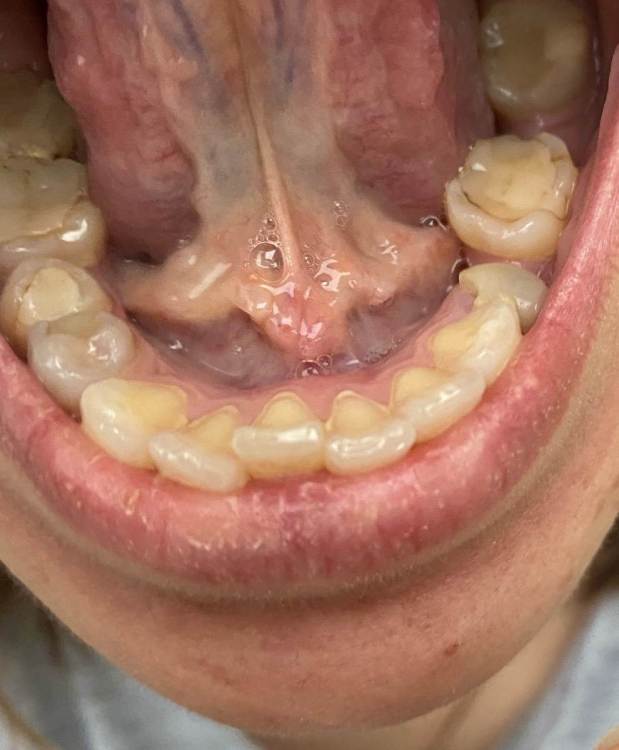

Екатерина-snk Опубликовано 17 февраля, 2022 Поделиться Опубликовано 17 февраля, 2022 (изменено) Добрый день . На уздечке языка появилось такое разрастание . С октября 2021 ( тогда и болела ковидом) . Не болит не растёт . Была у хирурга в пк говорит незнает что .. наблюдайте . Но город маленький , опыта не особо у врача . Подскажите что сделать ? Изменено 17 февраля, 2022 пользователем Екатерина-snk Ссылка на комментарий

red_butler Опубликовано 17 февраля, 2022 Поделиться Опубликовано 17 февраля, 2022 похоже на увеличенные протоки слюнных желез, это может быть после ОРВИ, пройдет само Ссылка на комментарий